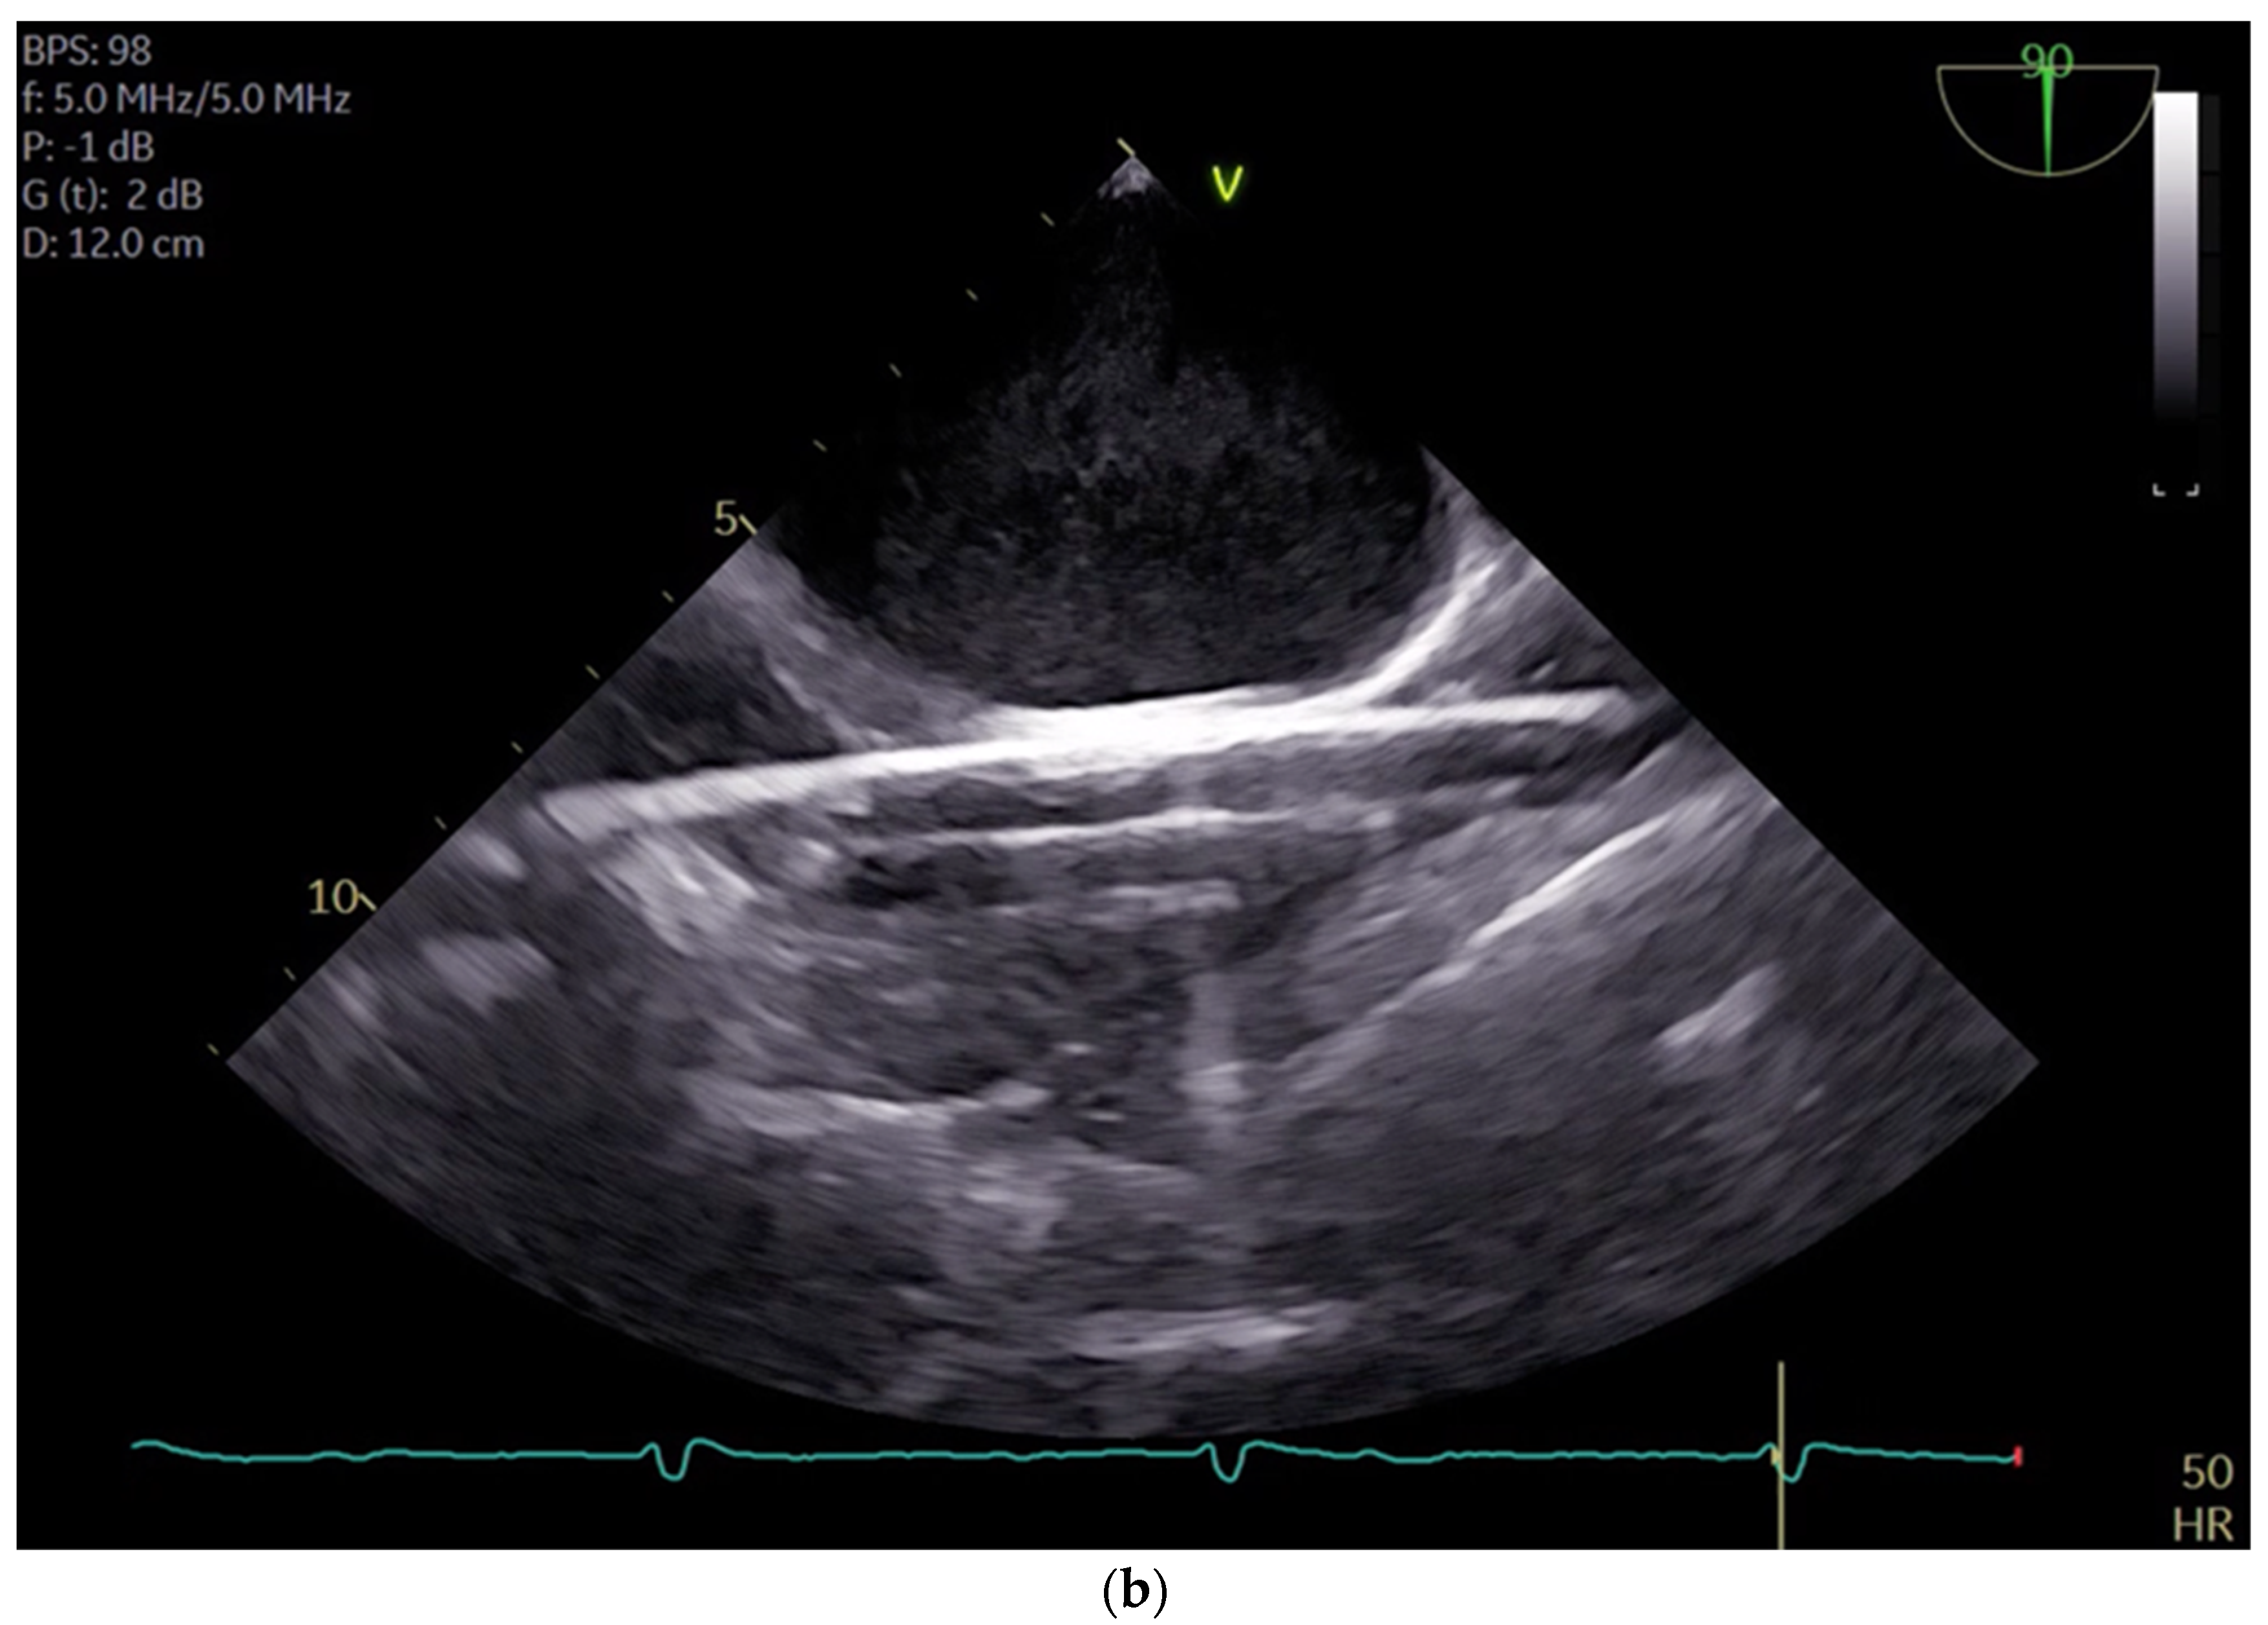

The cannulation of peripheral vessels for the purpose of establishing cardiopulmonary bypass (CPB) in minimal invasive cardiac surgery requires a meticulous approach. This is necessary in order to facilitate optimal redirection of blood flow. The femoral artery and vein, as well as the right internal jugular vein, are commonly employed vessels for cannulation [9]. These vessels offer accessible peripheral entry points for the insertion of cannulas, allowing for the efficient initiation of CPB while minimizing trauma to surrounding tissues [20]. Furthermore, advancements in surgical techniques have enabled the utilization of peripheral vessels such as the axillary artery, providing alternative cannulation sites that further enhance the minimally invasive nature of the procedure. This is achieved by potentially beneficial antegrade flow during cardiac procedures, which is currently under investigation [21]. By carefully selecting and cannulating these vessels, surgeons can effectively establish CPB with precision and safety, thereby facilitating successful outcomes in minimal invasive cardiac surgery. For femoral veins, a lengthy cannula (Bio-Medicus 23/25 FR multistage femoral venous cannula, Medtronic, Minneapolis, MN, USA) is introduced into the inferior vena cava, primarily via the right femoral vein, with echocardiographic guidance (refer to Videos S1 and S2). According to the established protocol, the guidewires are visualized. The venous wire and cannula are depicted through TEE in the midesophageal bicaval view (see Figure 1a,b). The arterial wire is visualized in the descending aortic short-axis (SAX) and long-axis (LAX) views (see Figure 2 and Video S3). The exclusion of malposition such as in the hepatic vein or interatrial septum perforation is carried out.

Figure 2.

Shows the arterial wire in the descending aortic short-axis (SAX) and long-axis (LAX).